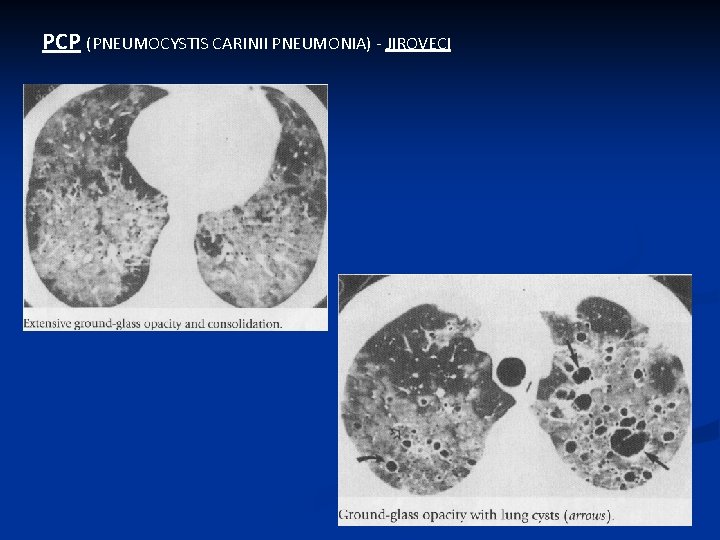

PCP (PNEUMOCYSTIS CARINII PNEUMONIA) - JIROVECI